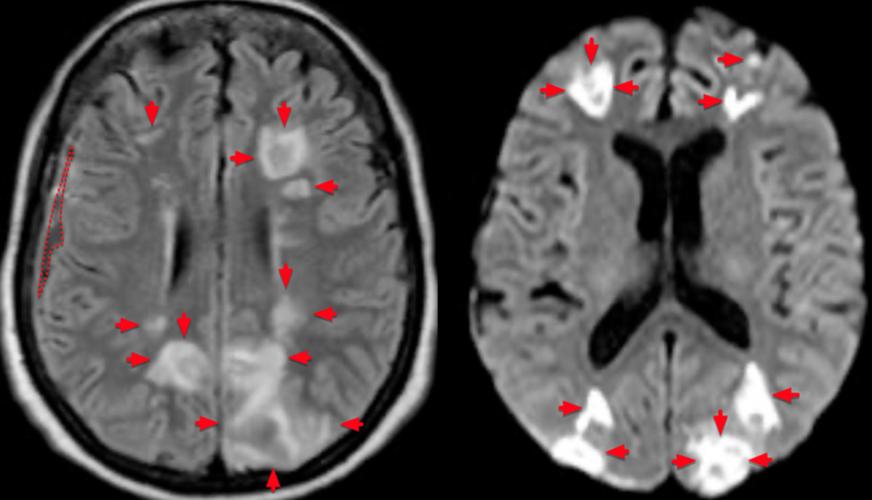

- FLAIR表现:在超早期(<6小时),FLAIR上可能完全看不到异常,或者仅有非常轻微的信号改变,这是FLAIR的一个局限性,也是为什么医生在怀疑急性脑梗时,会加做DWI(弥散加权成像)序列的原因,DWI对早期细胞毒性水肿极其敏感,发病几分钟就能显示出高信号。

- FLAIR表现:由于梗死区水分增多,在FLAIR图像上,这个区域会呈现明显的高信号(白色),因为FLAIR把周围的脑脊液“抹黑”了,所以这个白色的梗死灶在黑色的背景下显得非常清晰、边界锐利,这是FLAIR诊断脑梗的“黄金时期”。

- DWI (弥散加权成像) + ADC (表观弥散系数图):急性脑梗的“金标准”,在发病数分钟内就能发现异常,DWI高信号+ADC低信号是急性梗死的典型表现。